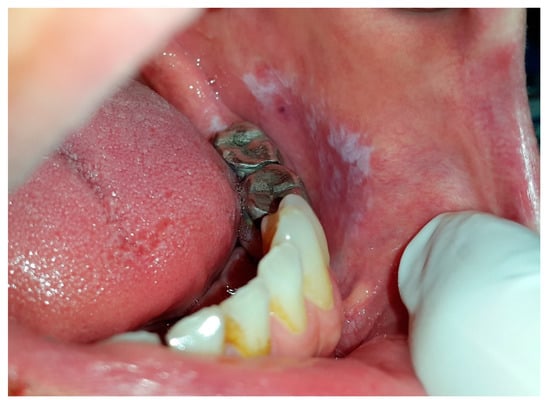

5.4. Lichenoid Contact Reactions

| LCR | NA | F | restricted to sites that are regularly in contact with dental materials such as buccal mucosa and lateral borders of the tongue | same reaction patterns as seen in OLP, that is, reticulum, papules, plaque, erythema, and ulcers | replacement of dental materials | NA |